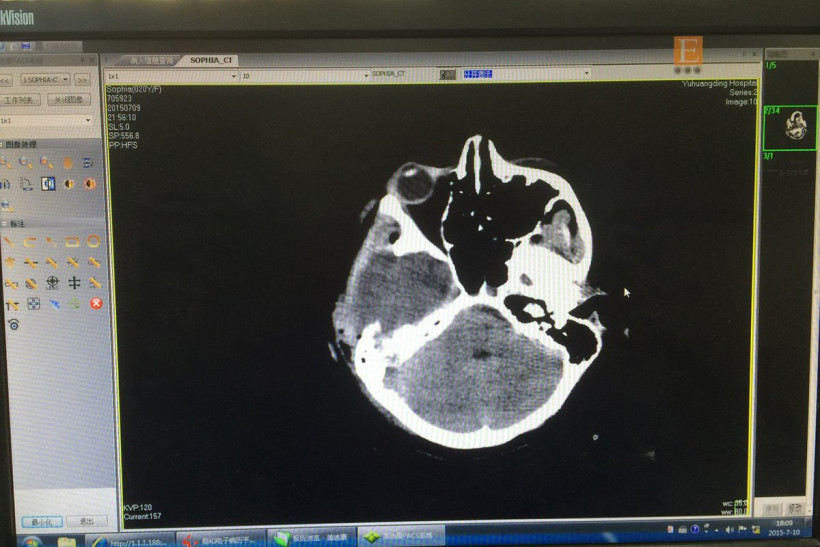

Падение в третьего этажа привело к серьезным травмам. Китайские медики диагностировали у девочки переломы пяток, голени и руки, повреждение позвоночника в поясничном отделе и ушиб головного мозга, который привел к появлению гематомы. Из-за нее у пострадавшей начало подниматься внутричерепное давление. В китайской клинике девочке удалили две черепные кости, чтобы снизить давление. Ее состояние оценивается как тяжелое, но стабильное.